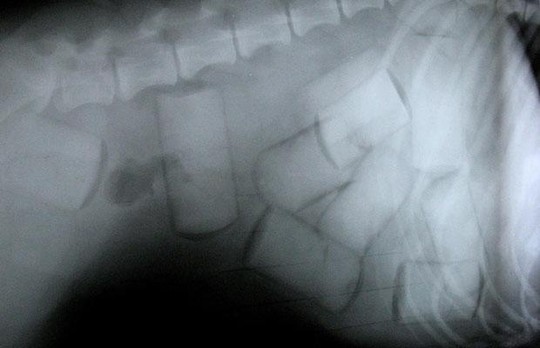

Cảnh sát Colombia cho biết bé gái đã nuốt hơn 100 viên thuốc con nhộng chứa ma túy vào bụng để chuyển đến châu Âu. Bé gái không được nêu tên đang được giám sát tại TP Cali, Tây Colombia sau khi ý đồ lợi dụng em để buôn lậu ma túy đã thất bại. Đây được xem là người buôn lậu ma túy nhỏ tuổi nhất từng bị phát hiện ở Colombia,

Chỉ huy cảnh sát Cali Hoover Penilla cho biết hôm 18-11 bé gái đã được phẫu thuật để lấy số ma túy nói trên khỏi bụng. Quan chức này nói thêm các dấu hiệu cho thấy bé gái sử dụng cách này qua mặt cơ quan chức năng theo hướng dẫn của người lớn. Cảnh sát Colombia đang truy tìm cha bé gái, người bị tình nghi có liên quan đến vụ việc.

Bé gái nuốt hơn 100 viên ma túy vào bụng. Ảnh: PA

Trước đó, mẹ bé gái cho biết cô và chồng không còn sống chung với nhau và bé gái đã đến ở với cha vào cuối tuần rồi. Khi trở về nhà với mẹ, bé gái cảm thấy buồn nôn suốt đêm và vẫn không khỏe vào sáng hôm sau. Người mẹ sau đó quyết định đưa em đến bệnh viện và các bác sĩ đã phát hiện hơn 100 viên thuốc con nhộng chứa ma túy trong bụng em.